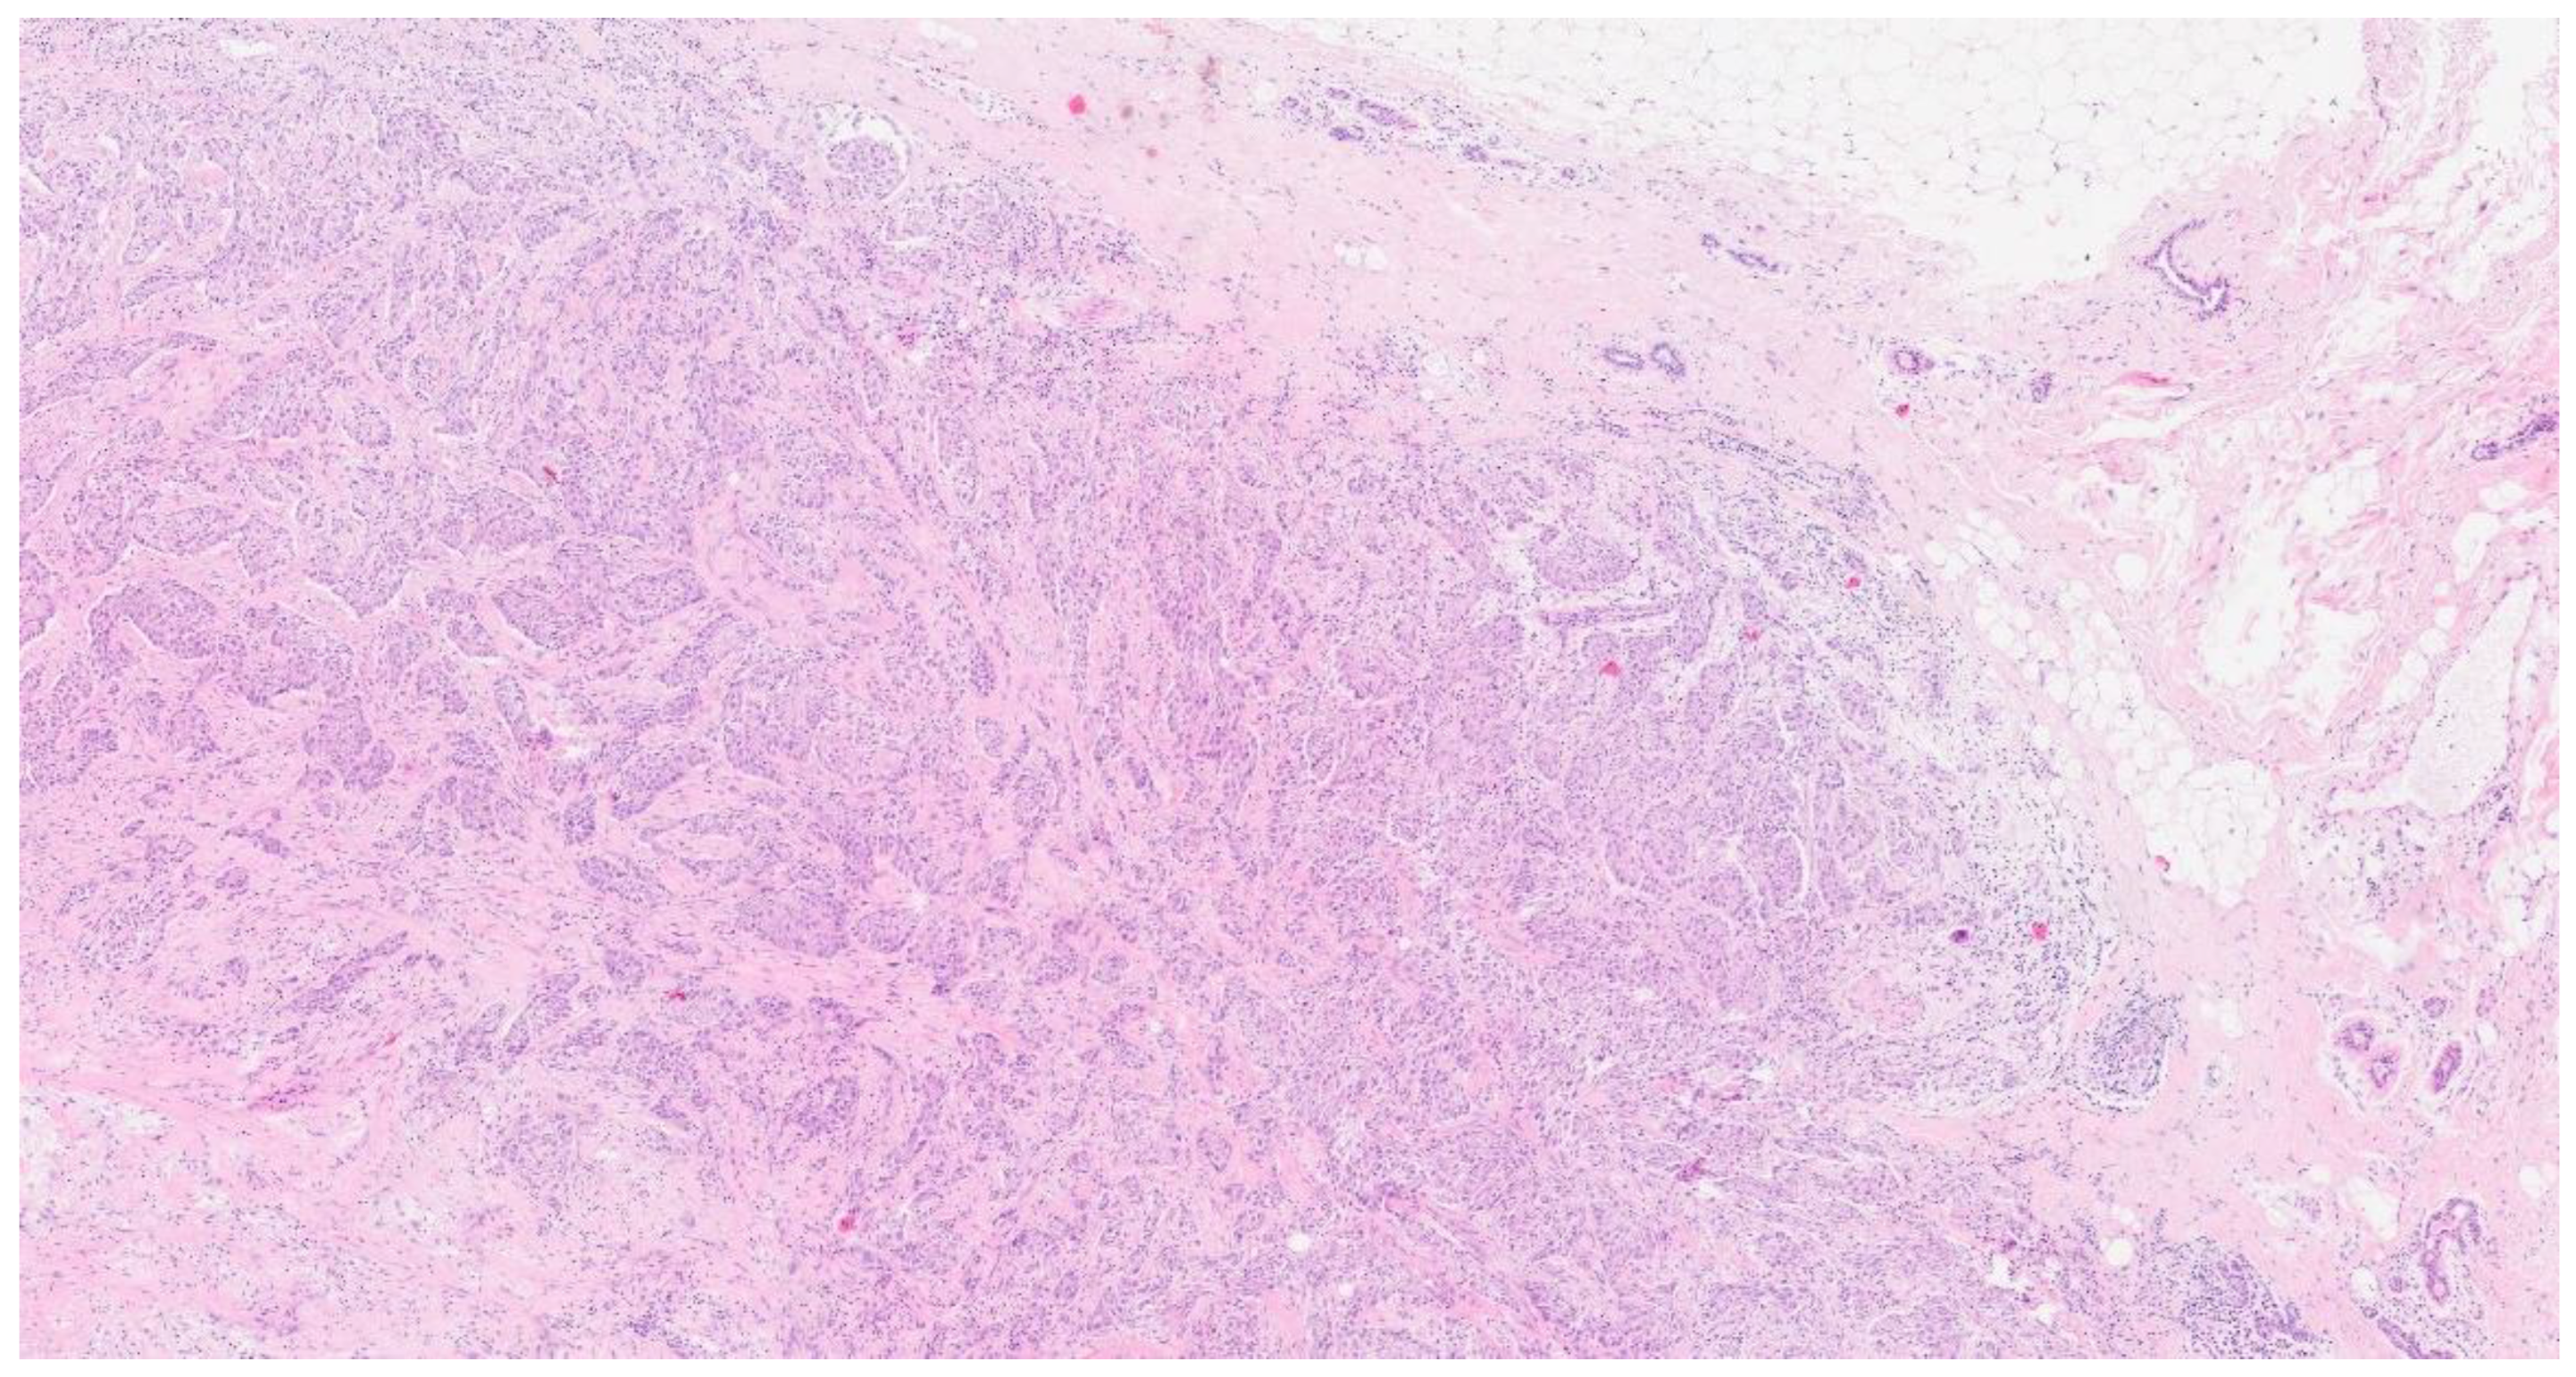

2. Case Presentation